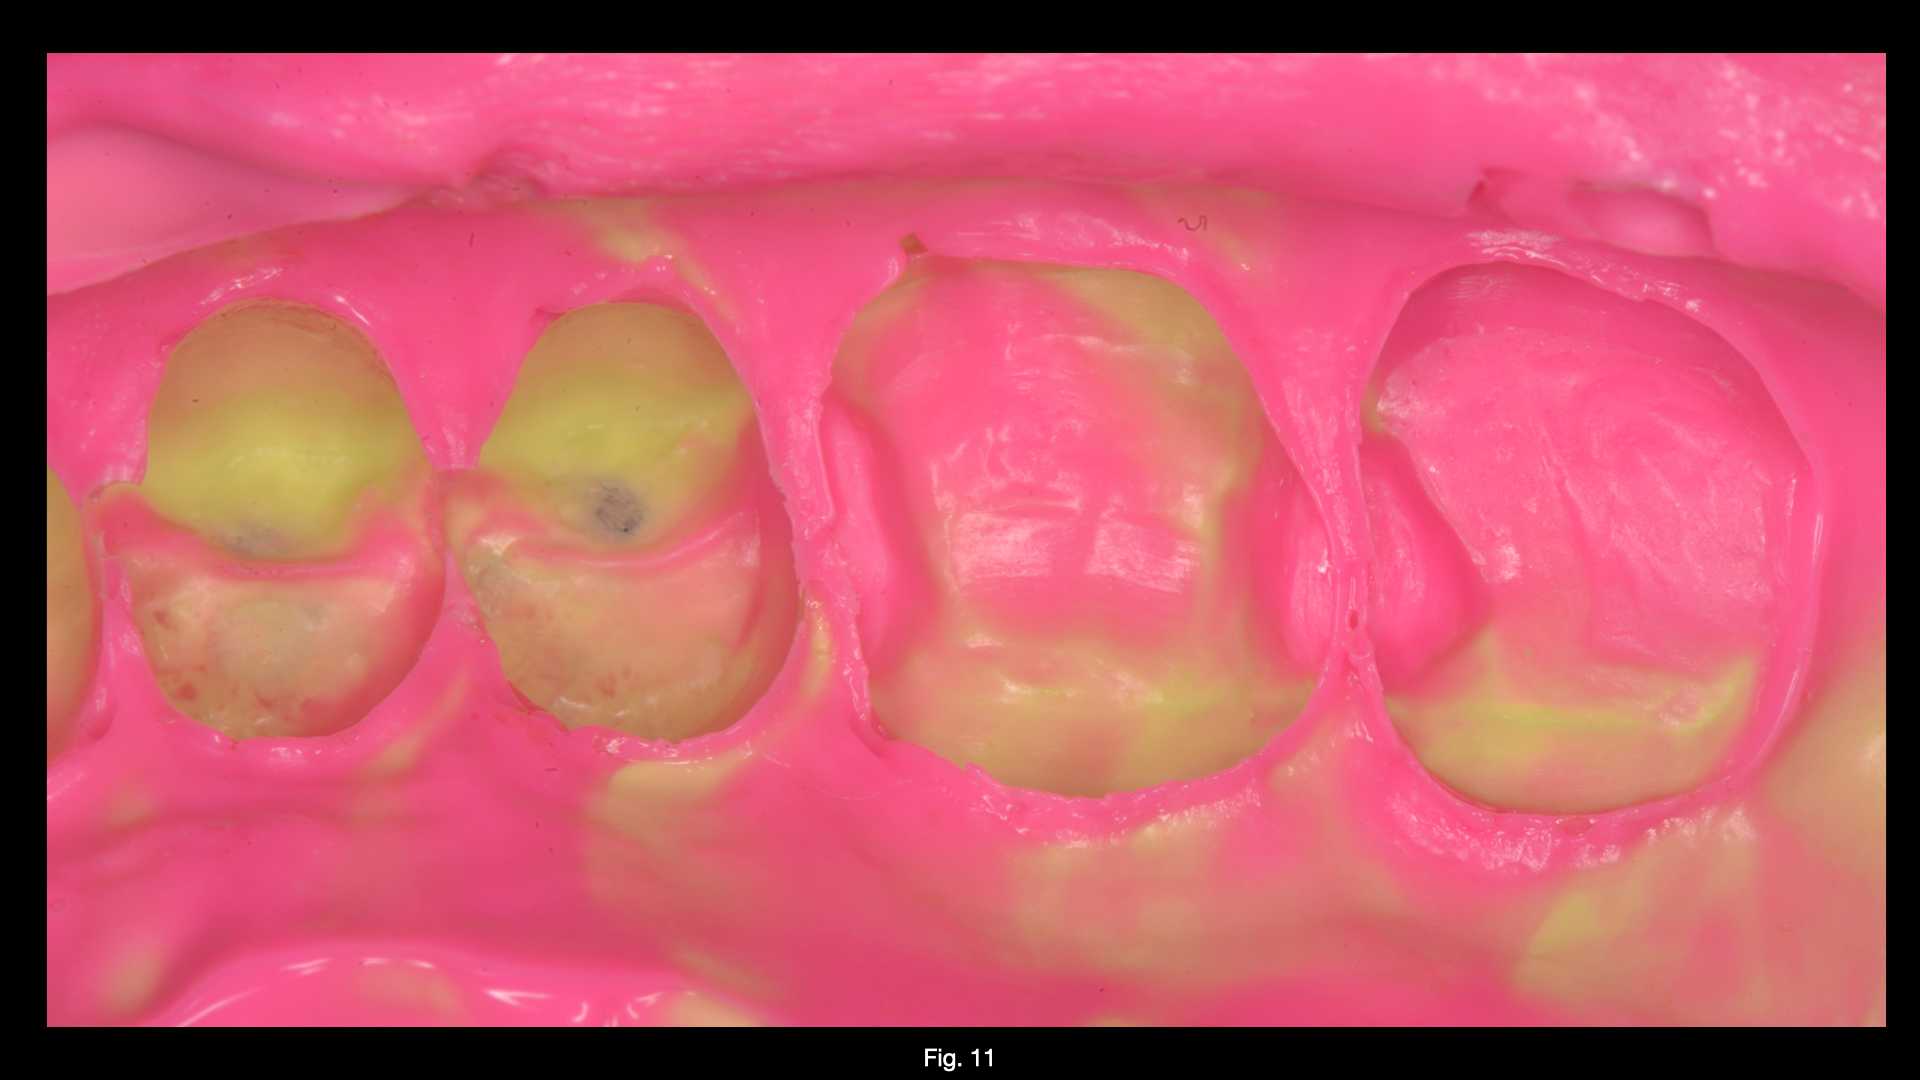

Dopo  avere  eseguito  i  restauri diretti tramite l’utilizzo del sistema sezionale  Garrison  Composi-tight 3D Fusion sono stati preparati gli elementi  1.7  e  1.6.  L’impronta  è stata rilevata con tecnica monofase bicomponente.  Al  successivo appuntamento, previo isolamento del  campo  operatorio  con  diga di  gomma,  i  manufatti  sono stati  cementati  con  composito preriscaldato.  In  questo  caso l’utilizzo  di  tale  composito  ha facilitato  le  fasi  di  rimozione  del cemento in eccesso a causa della diversa opacità tra prima e dopo la polimerizzazione . Fasi di rifinitura,lucidatura e brillantura sono state eseguite  prima  della  rimozione della  diga.  Minimi  aggiustamenti occlusali sono stati necessari.

11

12

Fig.11 Finale dopo procedure di rifinitura e lucidatura.Fig.12 Controllo a 1 mese. Visione Occlusale (rx allegata)